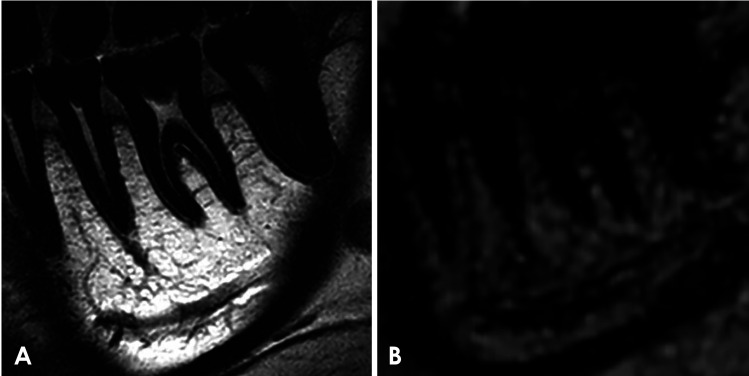

Purpose: This study aimed to assess the performance of 2-dimensional (2D) imaging with microscopy coils in delineating teeth and periodontal tissues compared with conventional 3-dimensional (3D) imaging on a 3 T magnetic resonance imaging (MRI) unit.

Materials and methods: Twelve healthy participants (4 men and 8 women; mean age: 25.6 years; range: 20-52 years) with no dental symptoms were included. The left mandibular first molars and surrounding periodontal tissues were examined using the following 2 sequences: 2D proton density-weighted (PDw) images and 3D enhanced T1 high-resolution isotropic volume excitation (eTHRIVE) images. Two-dimensional MRI images were taken using a 3 T MRI unit and a 47 mm microscopy coil, while 3D MRI imaging used a 3 T MRI unit and head-neck coil. Oral radiologists assessed dental and periodontal structures using a 4-point Likert scale. Inter- and intra-observer agreement was determined using the weighted kappa coefficient. The Wilcoxon signed-rank test was used to compare 2D-PDw and 3D-eTHRIVE images.

Results: Qualitative analysis showed significantly better visualization scores for 2D-PDw imaging than for 3D-eTHRIVE imaging (Wilcoxon signed-rank test). 2D-PDw images provided improved visibility of the tooth, root dental pulp, periodontal ligament, lamina dura, coronal dental pulp, gingiva, and nutrient tract. Inter-observer reliability ranged from moderate agreement to almost perfect agreement, and intra-observer agreement was in a similar range.

Conclusion: Two-dimensional-PDw images acquired using a 3 T MRI unit and microscopy coil effectively visualized nearly all aspects of teeth and periodontal tissues.